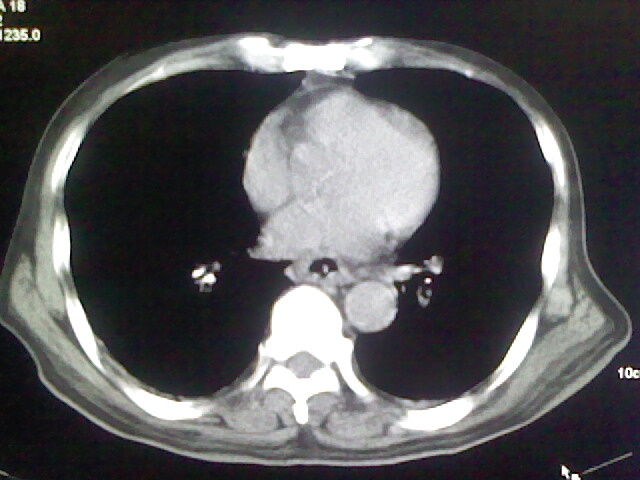

男,70岁,脑出血,长期卧床,左侧背部可触及肿块

右肺病灶考虑炎症性。

右肺病灶考虑炎症性

考虑右肺及左肺下叶炎症。

右肺及左肺下叶炎症。

考虑右肺及左肺下叶慢性炎症。

右侧肺部见片状密度增高影,边缘模糊。考虑炎症。另食管壁增厚。

右肺上叶前段病呈楔形,其尖端指向肺门,考虑肺动脉栓塞可能性大.